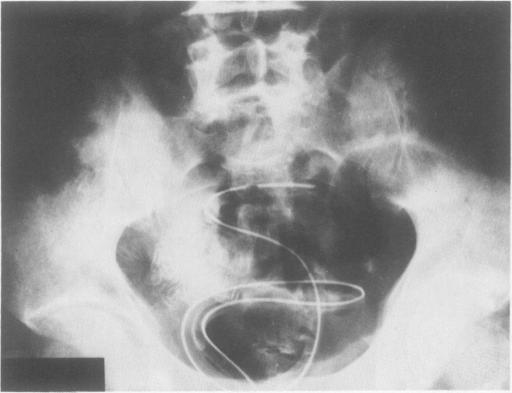

Colostomy is the traditional treatment for acute obstruction of the sigmoid colon. This entails two or three surgical procedures in a high-risk group of patients. Presented is a nonsurgical approach used in three patients with acute colonic obstruction. Decompression of the bowel was achieved with a tube introduced proximal to the obstruction with the aid of a flexible sigmoidoscope. In a fourth patient, in whom the obstruction was next to the splenic flecture, the procedure failed. In all instances where decompression was successful, a one-stage procedure--primary resection and anastomosis--was performed.

https://cdn.ncbi.nlm.nih.gov/pmc/blobs/fa67/1251093/55cf6a9dc9af/annsurg00097-0071-a.jpg